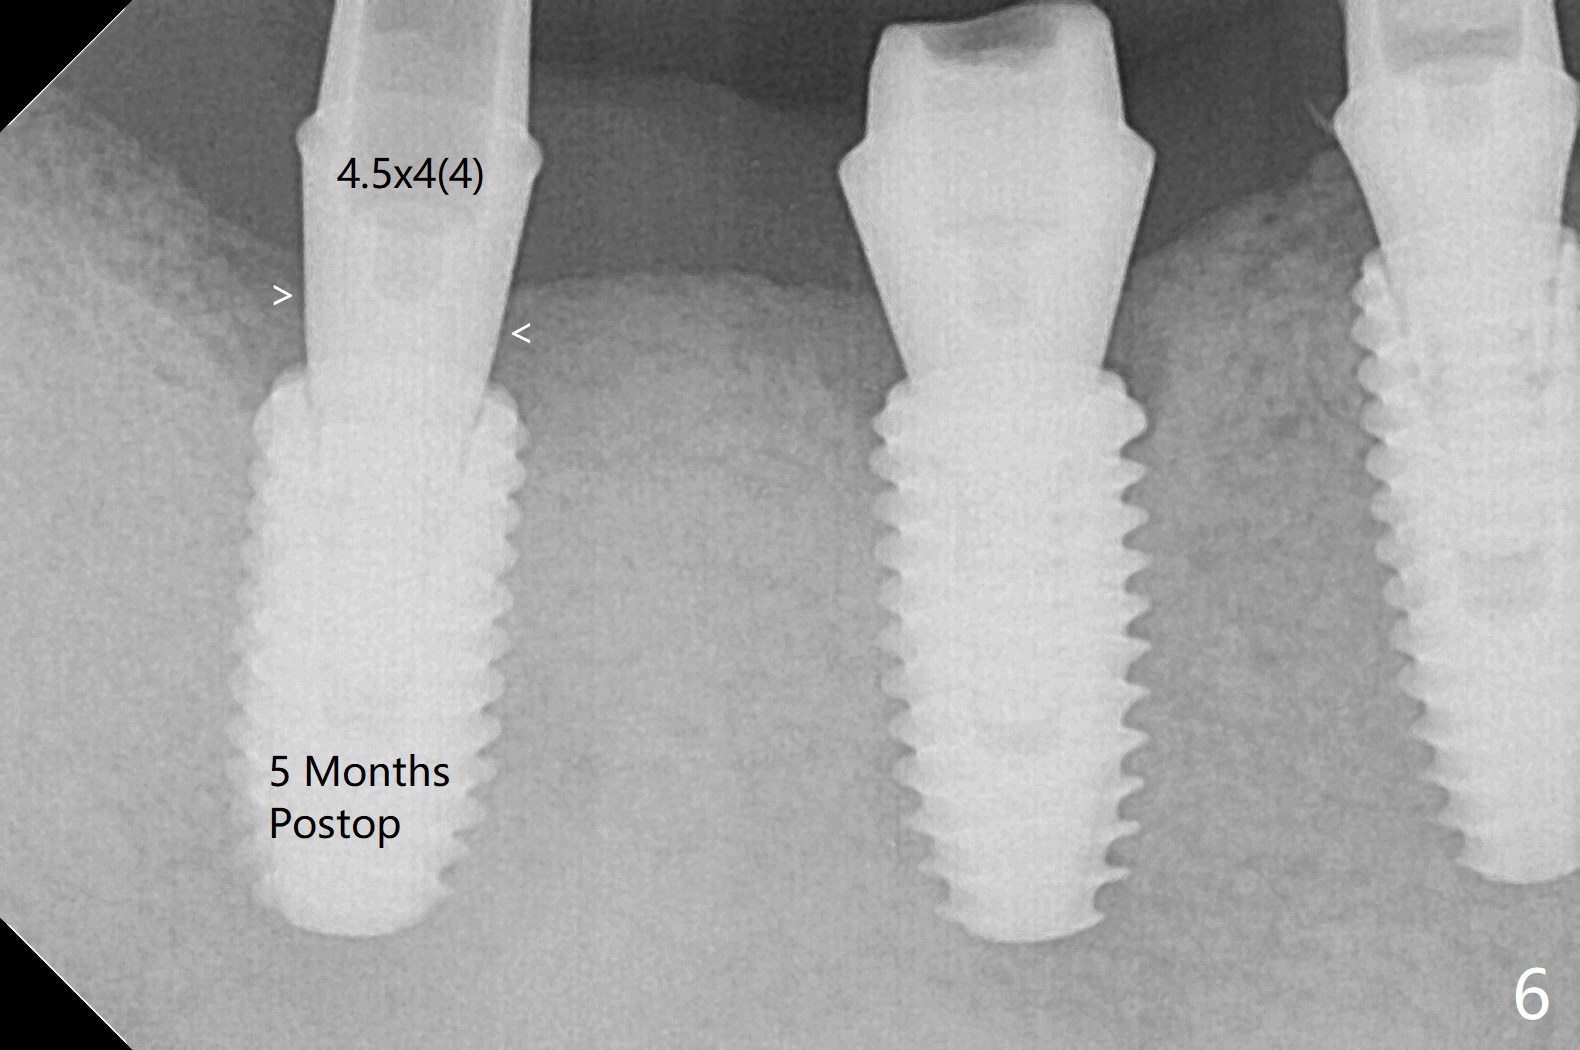

Five months post #31 implant removal with bone graft, osteotomy is initiated for a 5x10 mm implant using an existing guide. A question arises suddenly whether the bone height is reduced. Therefore a 4.5x10 mm dummy implant is placed with a fixture anchor placed at #30 (Fig.1 A). After using 4.5x8.5 mm drill with regular offset, a 5x10 mm definitive implant is placed with ~ 35 Ncm (Fig.2,3). After placement of the implant .5 mm deeper, a 8x6 mm healing abutment is placed, while the abutments return to #29 and 30 for splinted provisional (Fig.4). Two months later, the cemented abutment at #29 is loose (Fig.5) and retightened, but it remains incompletely seated for another 3 months (Fig.6). So is the one at #31 (Fig.6). After use of 4.6 and 5.6 mm bone profile drills, healing abutments are placed with apparently complete seating (Fig.7,8).